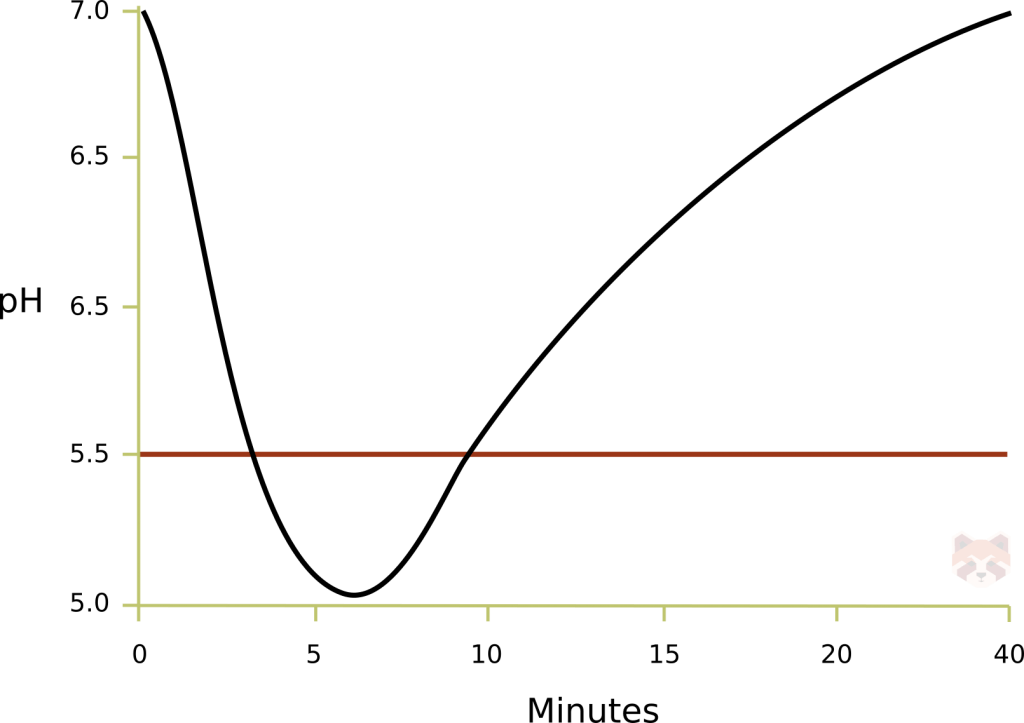

The Stephan curve depicts a rapid drop in oral pH after a meal or drink containing fermentable carbohydrates. The critical pH for enamel is 5.5, below which breakdown occurs. The critical pH for dentin is around 6.5. Recovery takes around 15-40 minutes. The frequency of available fermentable carbohydrates has more of an impact than quantity because it holds the curve below 5.5 longer. Saliva functions to buffer the fall in pH and provides the teeth with the mineral components (Ca, phosphate, F) to remineralize and strengthen tooth structure.